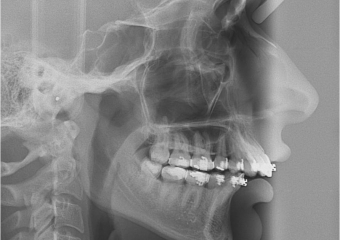

Telerradiografia após a cirurgia

Perfil apos Cirurgia (Controle 2 anos)